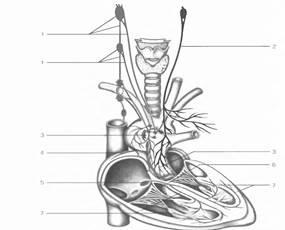

Randamentul plex toracice nervului aortic apare în peretele medial al venei cave superioare, partea din față și părțile posterioare ale aortei ascendente intre aorta si trunchiul pulmonar, înapoi, la stânga și la dreapta a trunchiului pulmonar. Conform fibrelor nervilor inimii adecvate nervoase senzoriale care constau din nervul vag și măduva spinării de la noduri, fibrele motorii autonome reprezentate de componentele simpatic preganglionari și postganglionare parasimpatice (Fig.1).

Fig.1. Inervare a inimii.